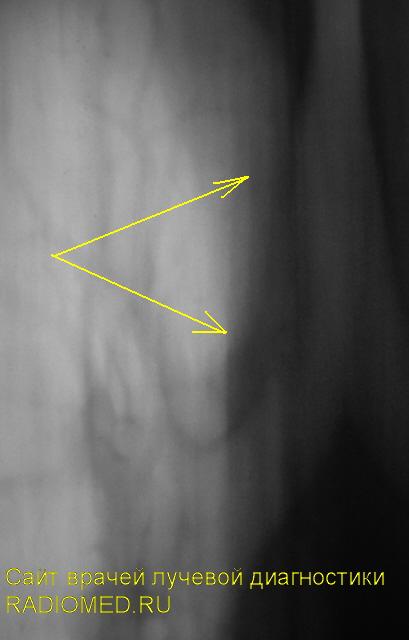

Очень смутило перибронхиальное уплотнение, помеченное жёлтыми стрелками.

3.jpg